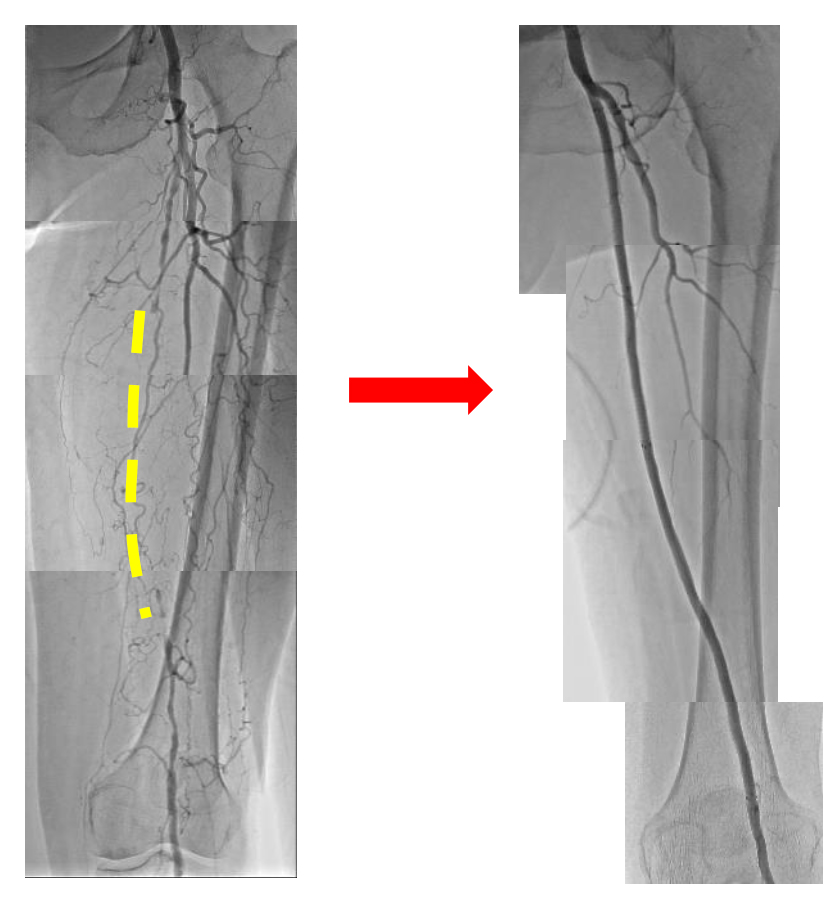

左浅大腿動脈の慢性閉塞をステントグラフト留置で治療

下肢PADは重篤化により潰瘍・壊疽を伴う包括的高度慢性下肢虚血(CLTI)を発症し、下肢切断に至るリスクが高く、下肢切断はADLやQOLまたはその後の生命予後をも悪化させます。当院のIVCセンターでは、血行再建を行う循環器内科や心臓血管外科、創傷処置を行う皮膚科・形成外科・整形外科、各種検査をサポートするコメディカルスタッフとともに大切断回避、歩行機能温存を目標としてチーム医療、集学的医療を行っています。

間歇性跛行、下肢の冷感・疼痛の自覚やABI低下、難治性潰瘍を認める場合は総合血管治療センターを受診してください。